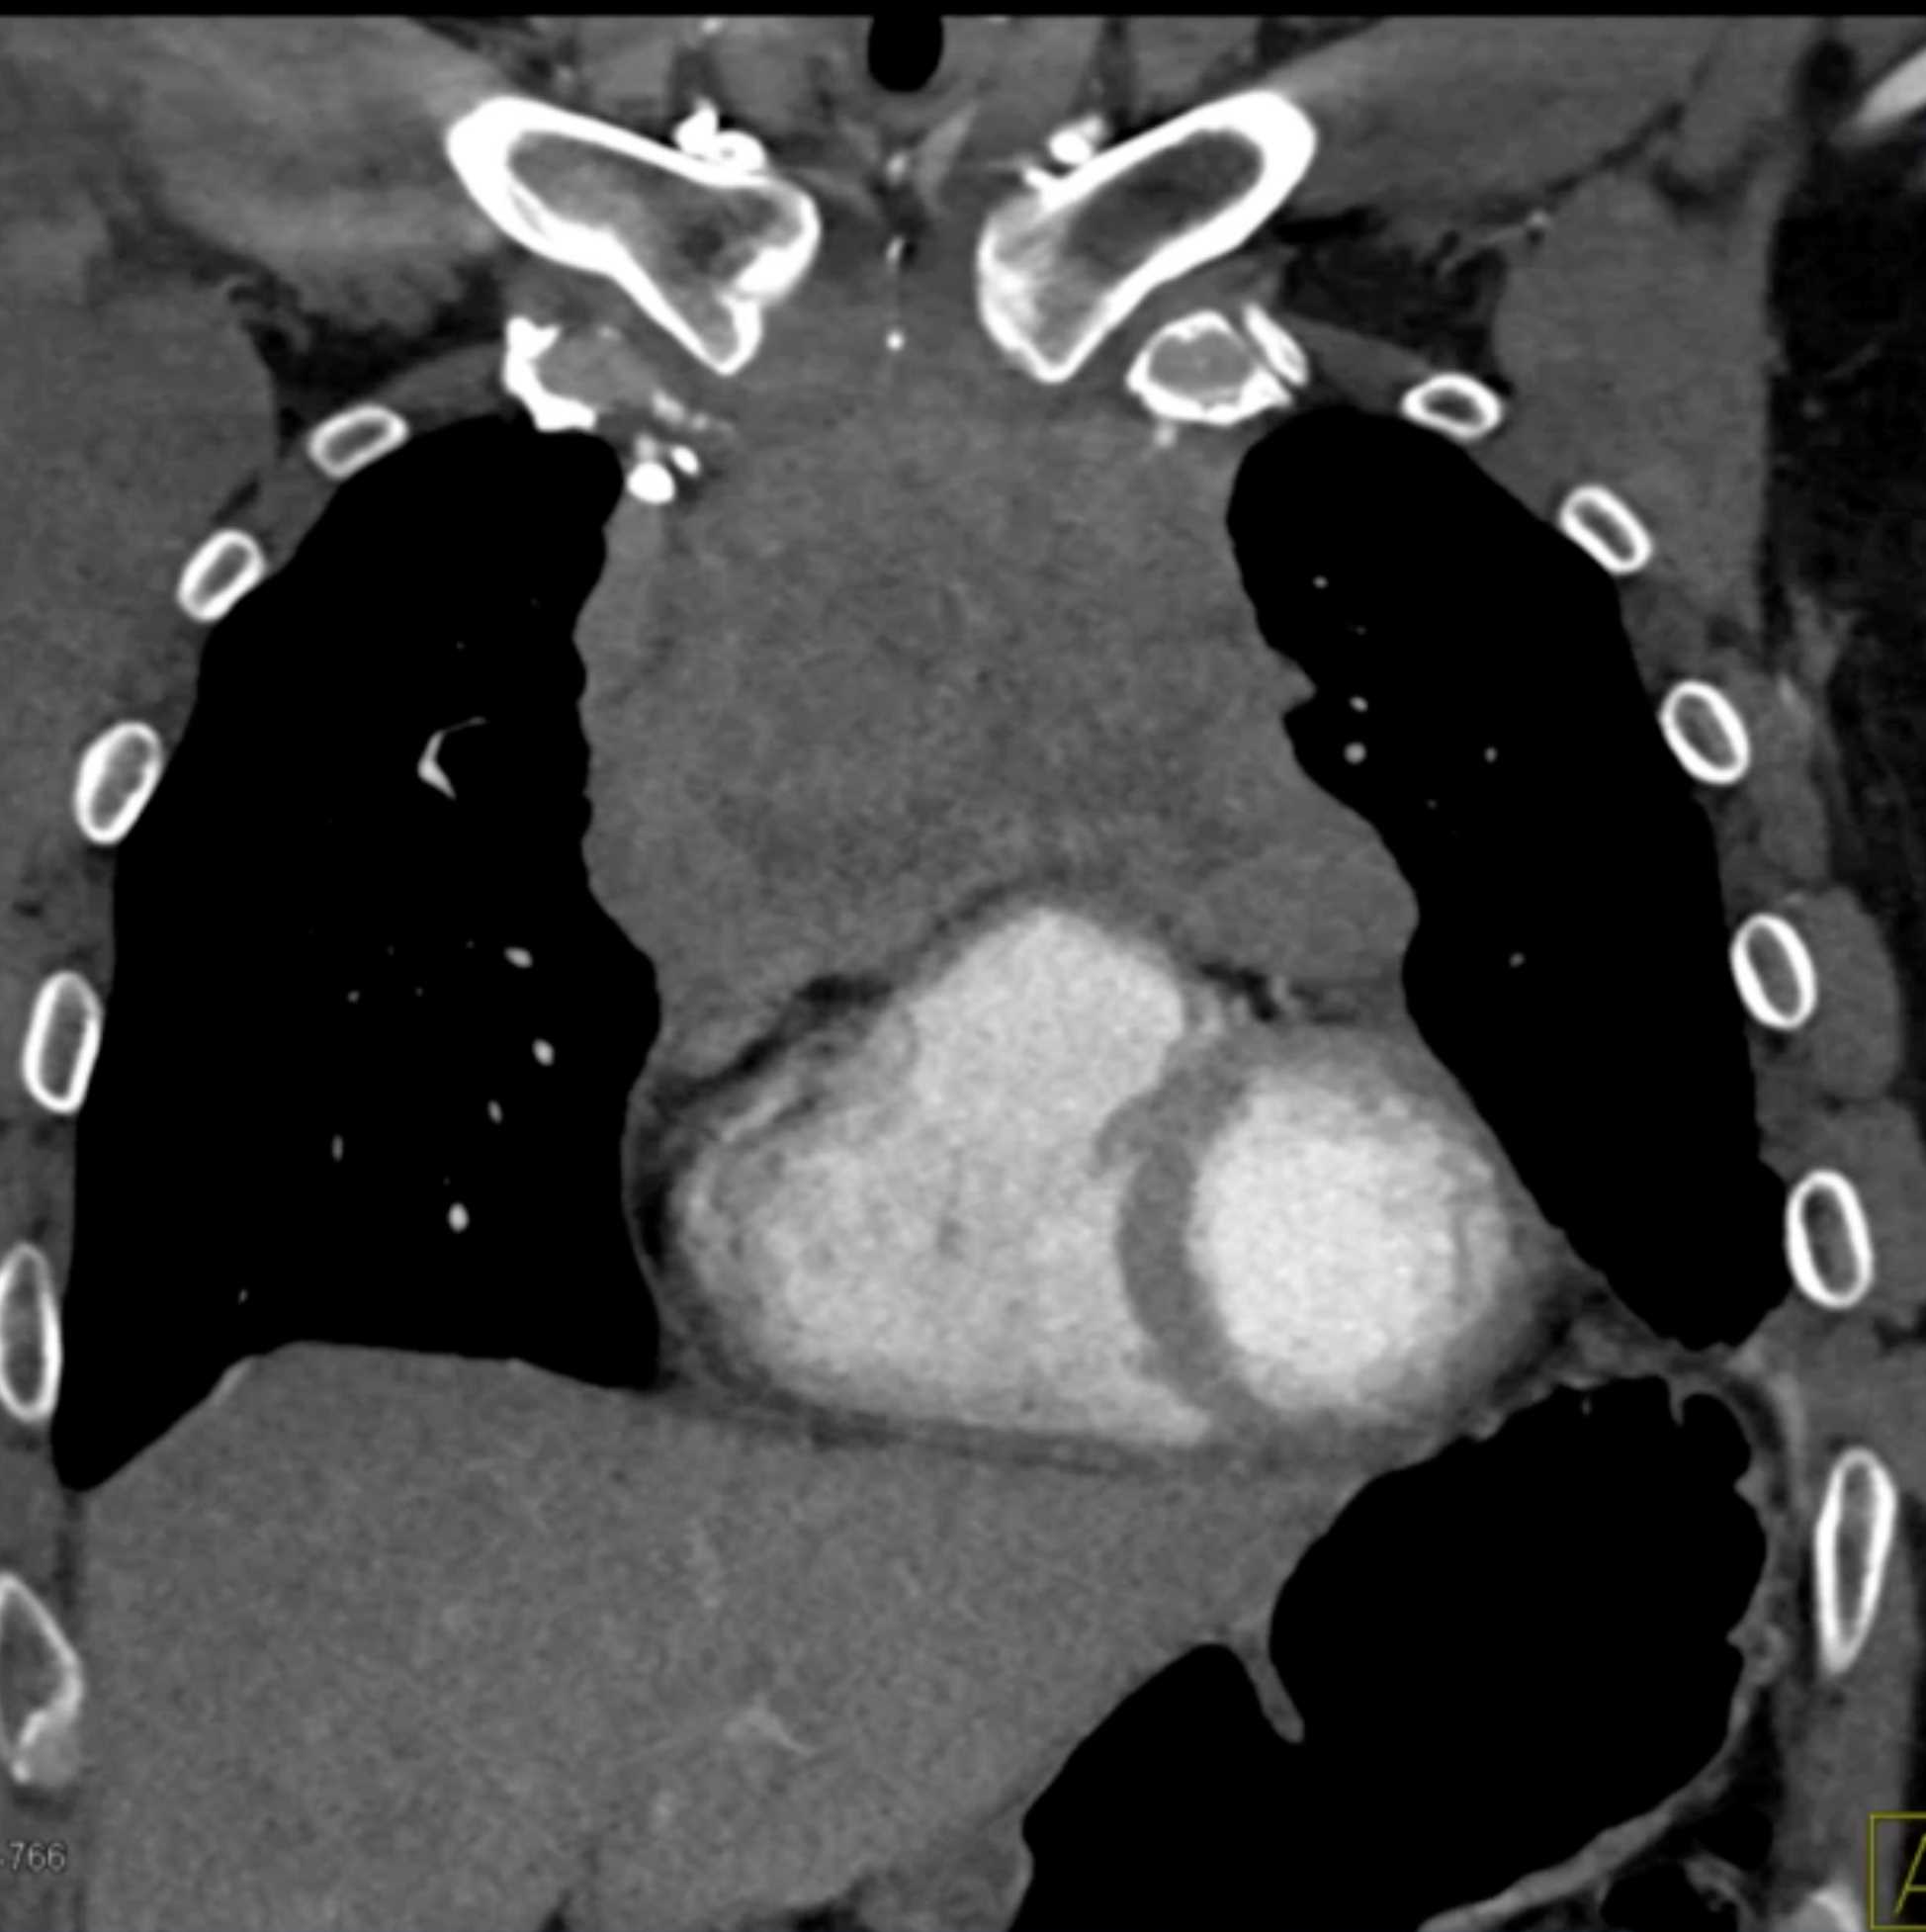

Thymic Carcinoma